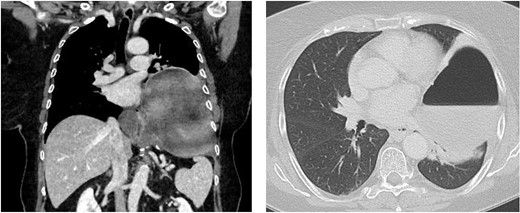

A 67-year-old female patient was admitted to the emergency department of our hospital with upper abdominal pain and vomiting. Previous medical history included a laparoscopic hiatal hernia repair in October 2018 due to a type III hiatal hernia and re-do surgery with mesh repair and a Toupet 270° posterior wrap due to a recurrence of the hiatus hernia with gastroesophageal reflux disease (GERD) in May 2019. Imaging studies revealed a new recurrence with total intra-thoracic stomach and compression of the left lower lung lobe (Fig. 1).

Chest/abdomen computed tomography showing a new recurrence with complete up-side-down stomach and compression of the left lower lung lobe.